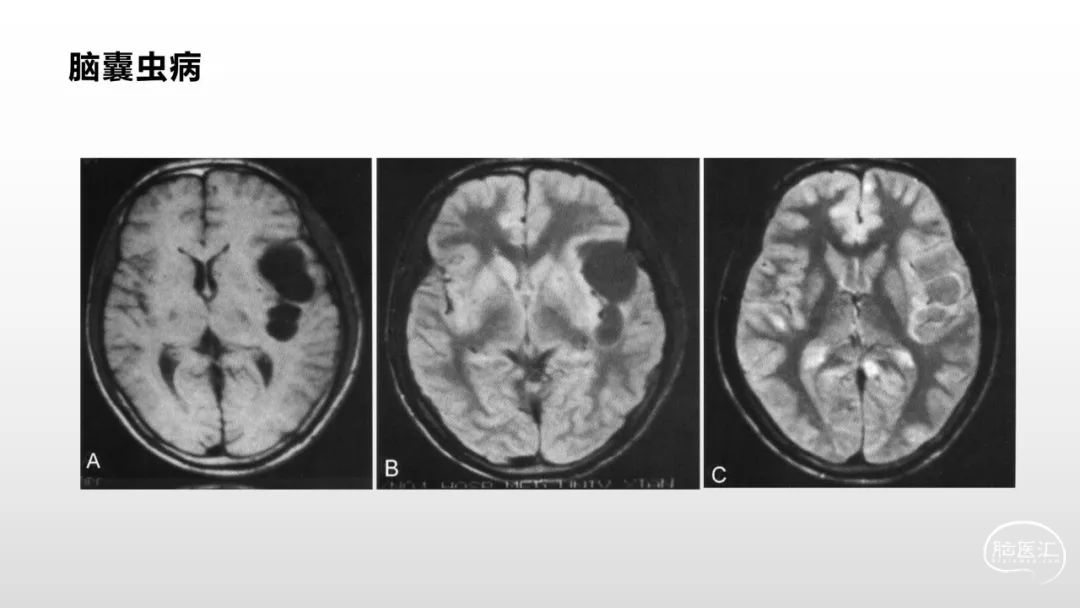

颅脑影像诊断基础知识讲座:脑膜病变